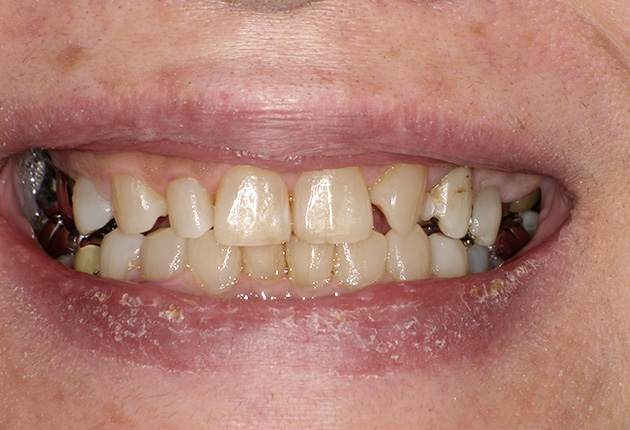

よく噛めず笑うと銀歯が目立つので気にされていました。

90分の治療で銀歯の状態からキレイな状態になります。噛み合わせの調整や審美面も使用しながら合わせます。

良く噛めて安心と、ご満足いただき大変嬉しく思います。笑顔も一層素敵になりました。

| 主訴 | ブリッジ脱離、しっかり噛めない |

| 診査診断 | 上顎歯牙欠損、歯周病、不良補綴、根尖性周囲炎。 不正咬合により噛み合わせのバランスが悪い事が原因により咬合治療が必要。 |

| 治療内容 | 欠損部インプラント 不正咬合に対し不良補綴のやり直しと合わせて咬合再構築 |